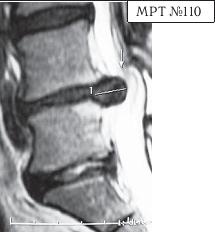

На МРТ № 111 поясничного отдела позвоночника отмечается рецидив — грыжа межпозвонкового диска LIV-LV после трёх операций. Даже если прооперировать в четвёртый раз, то это всё равно не решит проблемы и не добавит здоровья данному пациенту, так как неизбежно возникнут осложнения в вышележащих сегментах LI—LII LIII—LIV в силу биомеханических нарушений в позвоночнике и выраженных дегенеративно-дистрофических изменений в указанных сегментах. На МРТ № 112 поясничного отдела позвоночника отмечается рецидив — секвестрированная грыжа межпозвонкового диска в сегменте LIV-LV после четырёх операций. Здесь, как говорится, без комментариев. К сожалению, в жизни бывает так, что даже профессиональный специалист иногда вместо пользы может принести серьёзный вред пациенту, исключительно из-за шаблонного подхода. Как ни парадоксально это звучит, но это так. Приведу один пример по этому поводу. Ко мне на приём привели женщину. Привели в буквальном смысле этого слова под руки, при этом она ещё дополнительно опиралась на тросточки. Первое о чём я подумал, когда увидел, с какой осторожностью её ведут и как она переставляет ноги, что у данной пациентки как минимум перелом позвоночника с травмой спинного мозга или как максимум — опухоль в спинномозговом канале. Но в данном случае причина оказалось совсем иной. На протяжении последних десяти лет у пациентки периодически возникали боли в поясничном отделе позвоночника. Она к ним привыкла и не переживала по этому поводу, так как боли были умеренные, быстро проходили и довольно легко переносились. Но полтора года назад, после физической нагрузки, появились сильные, тянущие боли в ноге. Женщина вынуждена была обратиться в больницу по месту жительства. Пациентку направили к невропатологу, который, осмотрев её, сделал предположение, что возможно у неё «грыжа межпозвонкового диска» и направил женщину на МРТ. Так вот, сделав МРТ (МРТ №№ 113–115), женщина вернулась со снимками к невропатологу. Он ознакомился с результатами обследования и вместо того чтобы назначить ей консервативные методы лечения при таком диагнозе, направил её… на консультацию к нейрохирургу. Нейрохирург между прочим специалист высокого класса, с большим опытом работы, спасший много человеческих жизней. Однако и он, ознакомившись с результатами обследования, осмотрев пациентку, сделал вывод, что необходима срочная операция по удалению грыжи межпозвонкового диска в сегменте LIV-LV.